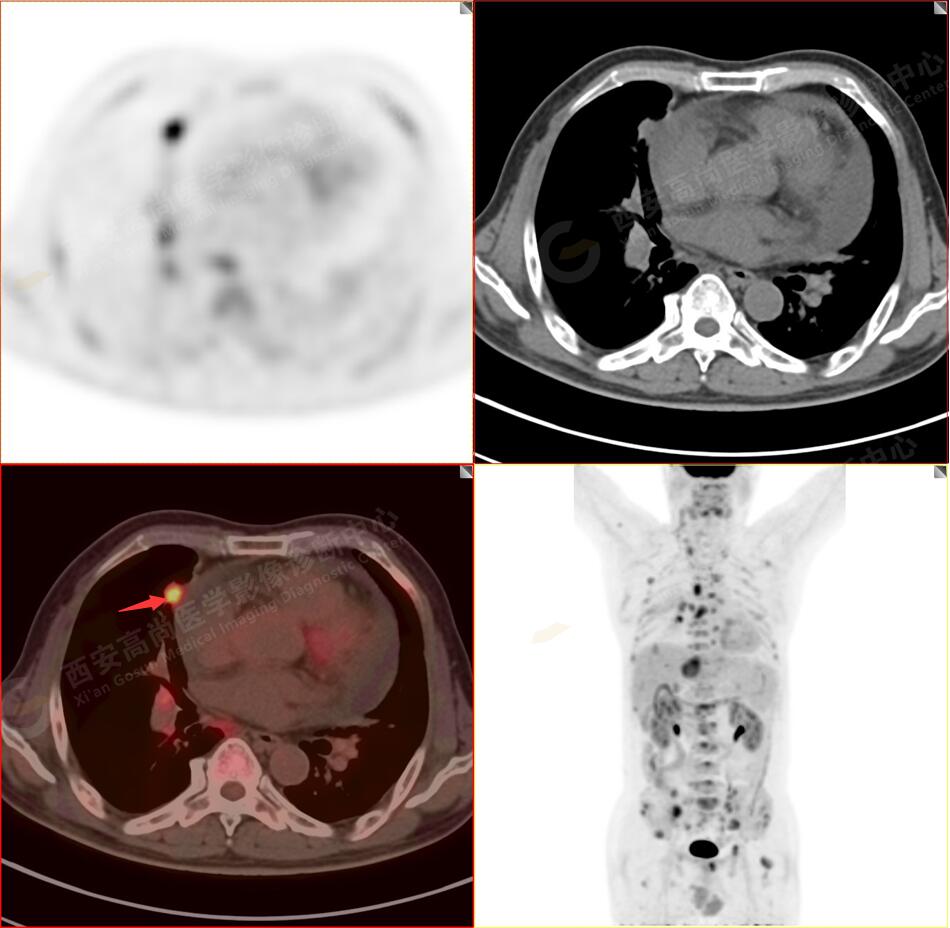

2.以下為全身多發(fā)轉移灶

2.雙肺內(nèi)彌漫性分布大小不等實性小結節(jié)灶及粟粒狀高密度影,均未見FDG代謝明顯異常增高,均多考慮為癌性淋巴結炎及轉移性病變。

5.右側肱骨上段、左側肩胛骨、右側鎖骨胸骨端、胸骨、雙側多發(fā)肋骨、脊柱多發(fā)椎體及附件、雙側髂骨、雙側髖臼、雙側恥骨、雙側肱骨上段多發(fā)成骨性病變,呈不同程度FDG代謝異常增高,考慮為多發(fā)骨轉移瘤。